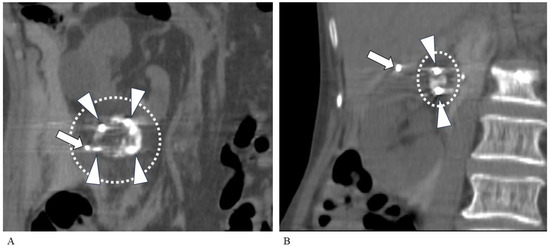

2.2. TAE Technique

2.3. PCA Technique

3.2. Transarterial Embolization

3.3. Percutaneous Cryoablation